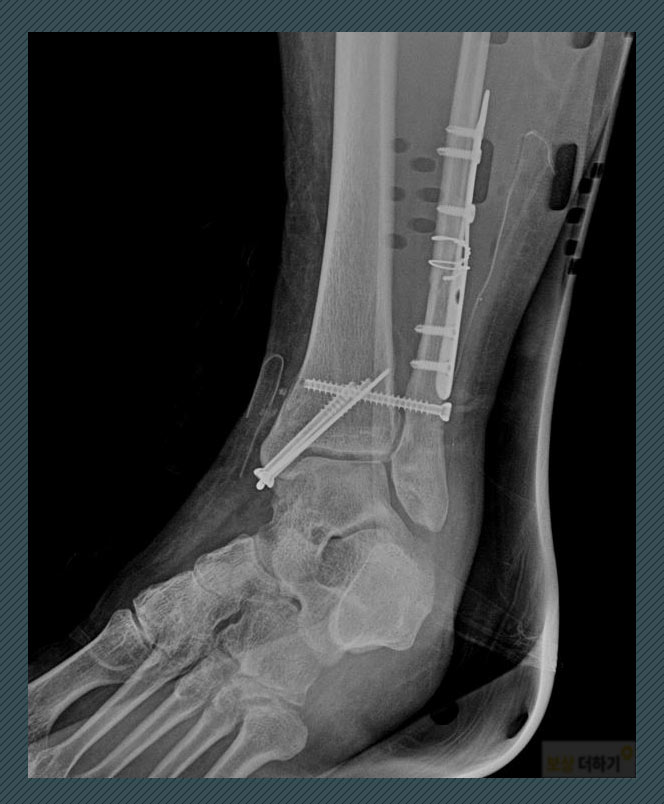

모든 발목 골절이 수술을 필요로 하는 것은 아니지만 사례자의 경우, 안정적인 뼈의 유합을 위해 금속판 내고정술을 시행 받으셨습니다.

수술을 통해 유합은 잘 되었지만, 금속물이 골절된 뼈의 위아래로 고정되어 있기 때문에 발목 관절이 예전처럼 잘 움직일 수는 없었습니다. 시간이 지나 핀 제거 수술을 했고, 경과를 보며 재활의 강도를 높이며 회복을 위해 노력하셨어요. 사고 몇 년 후 - 후유장해 -